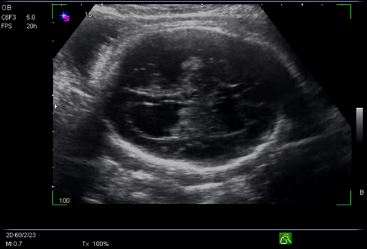

Aunque no se conoce el nivel de incidencia, el embarazo ectópico en cicatriz de cesárea previa puede ocurrir y se presenta como todo un reto para el personal médico especialista que trata el caso.

Es considerada una forma novedosa y potencialmente mortal de implantación anormal de un saco gestacional dentro del miometrio y el tejido fibroso de la cicatriz.